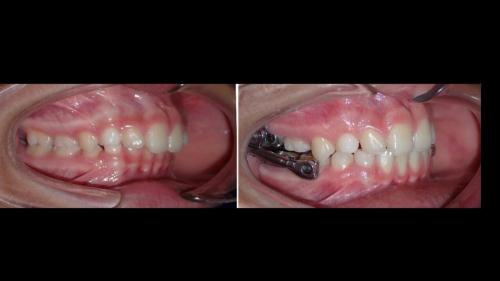

Galería de Sonrisas

large-Ortodoncia Lingual

large-Ortodoncia lingual invisible

large-Lingual